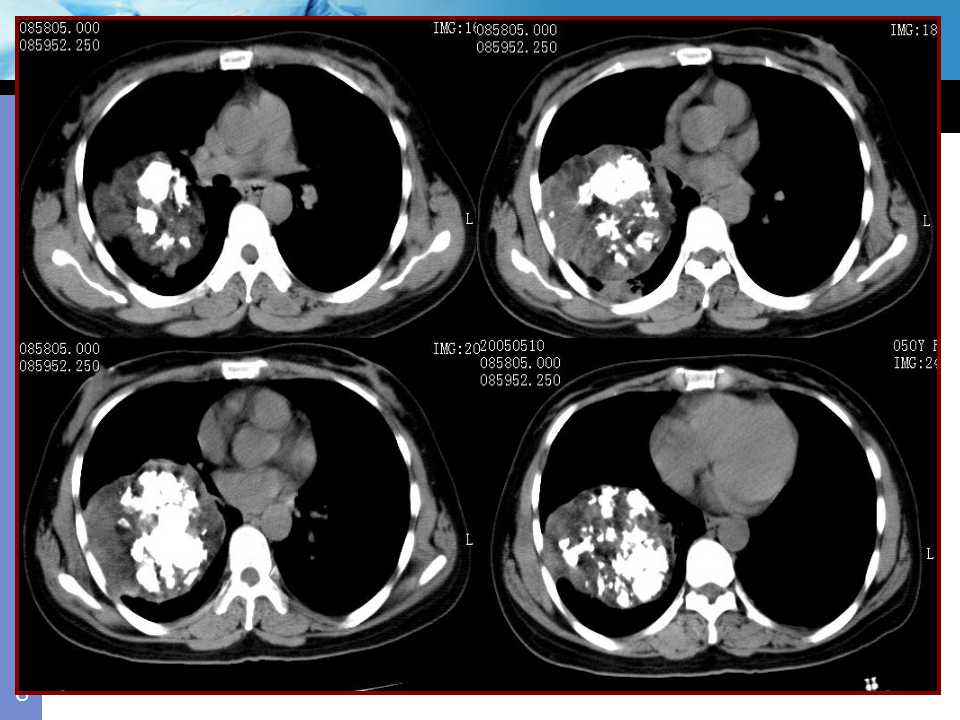

肺癌影像诊断